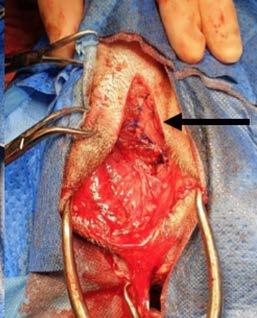

A lumpectomy was performed the following week. The lumpectomy was essentially a scrotal ablation, with removal of the lump through the scrotal ablation site. Care was taken not to separate the lump from the surrounding tissue. The vas deferens was located, attached to the distal edge of the lump. The vas deferens and tunica were ligated as deep as possible. The lump was submitted for histopathology.

Figure 3. Mass Intra-operative photograph Authors’ views are not necessarily those of the CVE

Figure 3. Intra-operative photographs of perineal herniorrhaphy using autologous rectus abdominis aponeurosis (Black Arrow) with internal obturator muscle transposition.